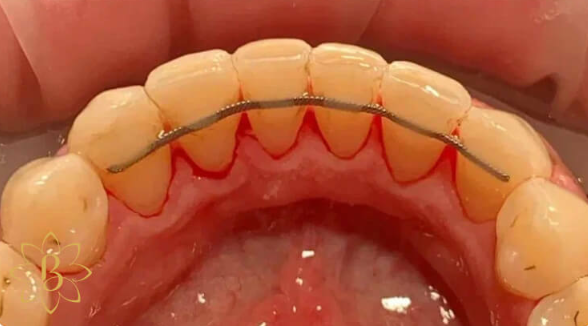

Профессиональная гигиена особенно важна при ортодонтическом лечении, ведь в повседневной жизни, дома, очень сложно поддерживать должный уровень гигиены полости рта! Даже если вы используете ирригатор и специальные ёршики! В нашей рубрике «до/после» вы видите то, что может быть с зубами при лечении брекетами, если не проводить своевременную чистку у врача-стоматолога. Марухно Дарья Александровна провела профессиональную чистку в несколько этапов, чтобы вернуть пациентке белизну ее собственных зубов! Брекет-система была поставлена не в нашей клинике, и почему пациентка не обратилась за профессиональной помощью раньше-вопрос) Но в данном случае, главное – итог! Кровоточивость после даже обычной чистки в такой клинической ситуации – естественный результат. Ведь обильный зубной налёт и зубной камень вызывают воспаление дёсен в виде гингивита, а порой даже пародонтита.

Доктор: Марухно Дарья Александровна

Профессиональная гигиена для детей с брекет-системами